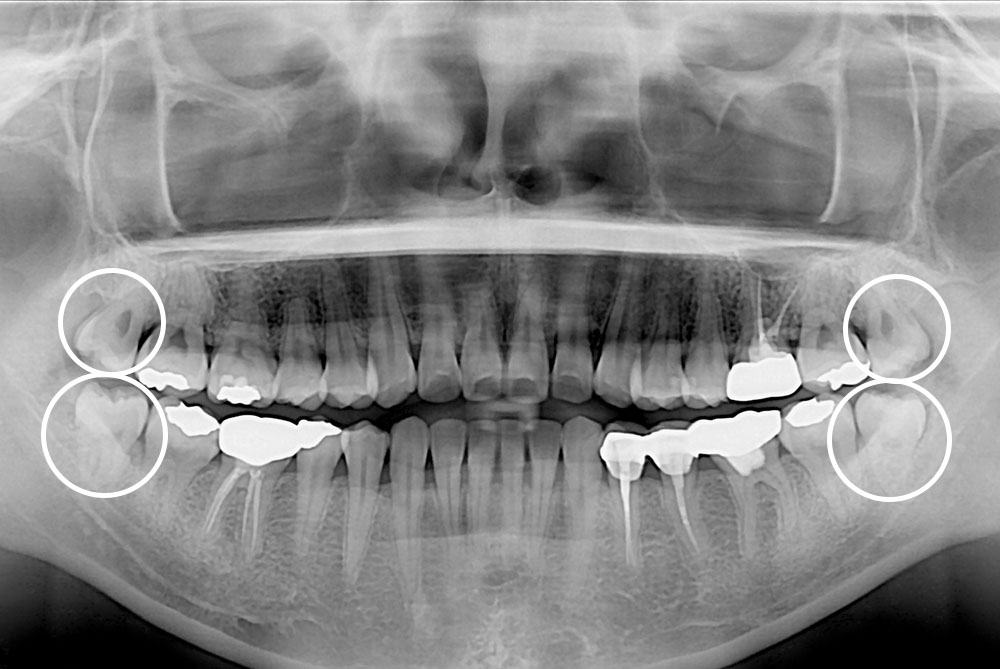

[사랑니] 매복 사랑니 발치

치료전 : 2019-09-04